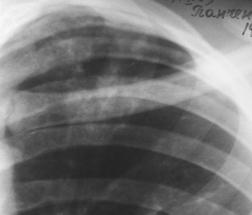

Рис.2. Инфильтрат. Просветление обозначает наличие деструкции (стрелка). Вокруг – множество очагов бронхогенного отсева